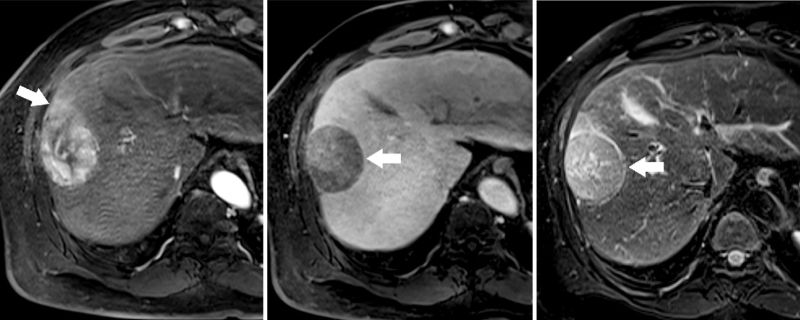

.jpg)

MRI cho độ nhạy cao hơn so với CT trong trường hợp tổn thương nhỏ <1cm

Cộng hưởng từ (MRI): Có độ tương phản mô mềm cao, đặc biệt hiệu quả trong phát hiện tổn thương nhỏ (<1cm). Khi sử dụng thuốc tương phản đặc hiệu như Primovist, MRI cho độ nhạy cao hơn (82%) so với CT. Đồng thời, phương pháp này không sử dụng tia xạ và phù hợp theo dõi sau điều trị.